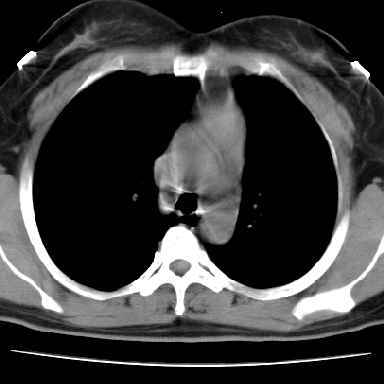

偏心性厚壁空洞,壁结节,胸膜肥厚粘连,双肺多发性小结节灶。这么多典型征象,即使错了也错的有道理!

病灶与临床特点:1 位于下肺外围.2 与胸膜关系密切并明显胸膜反应.3 空洞内壁虽见壁结节,但还是较光滑.4 病灶周围明显渗出.5 另肺内多发小结节.6 临床症状轻,发病时间短.综合考虑:肺内特殊感染(霉菌感染).

1、癌性空洞,右肺小结节考虑转移。2、曲霉菌感染?右侧为播散